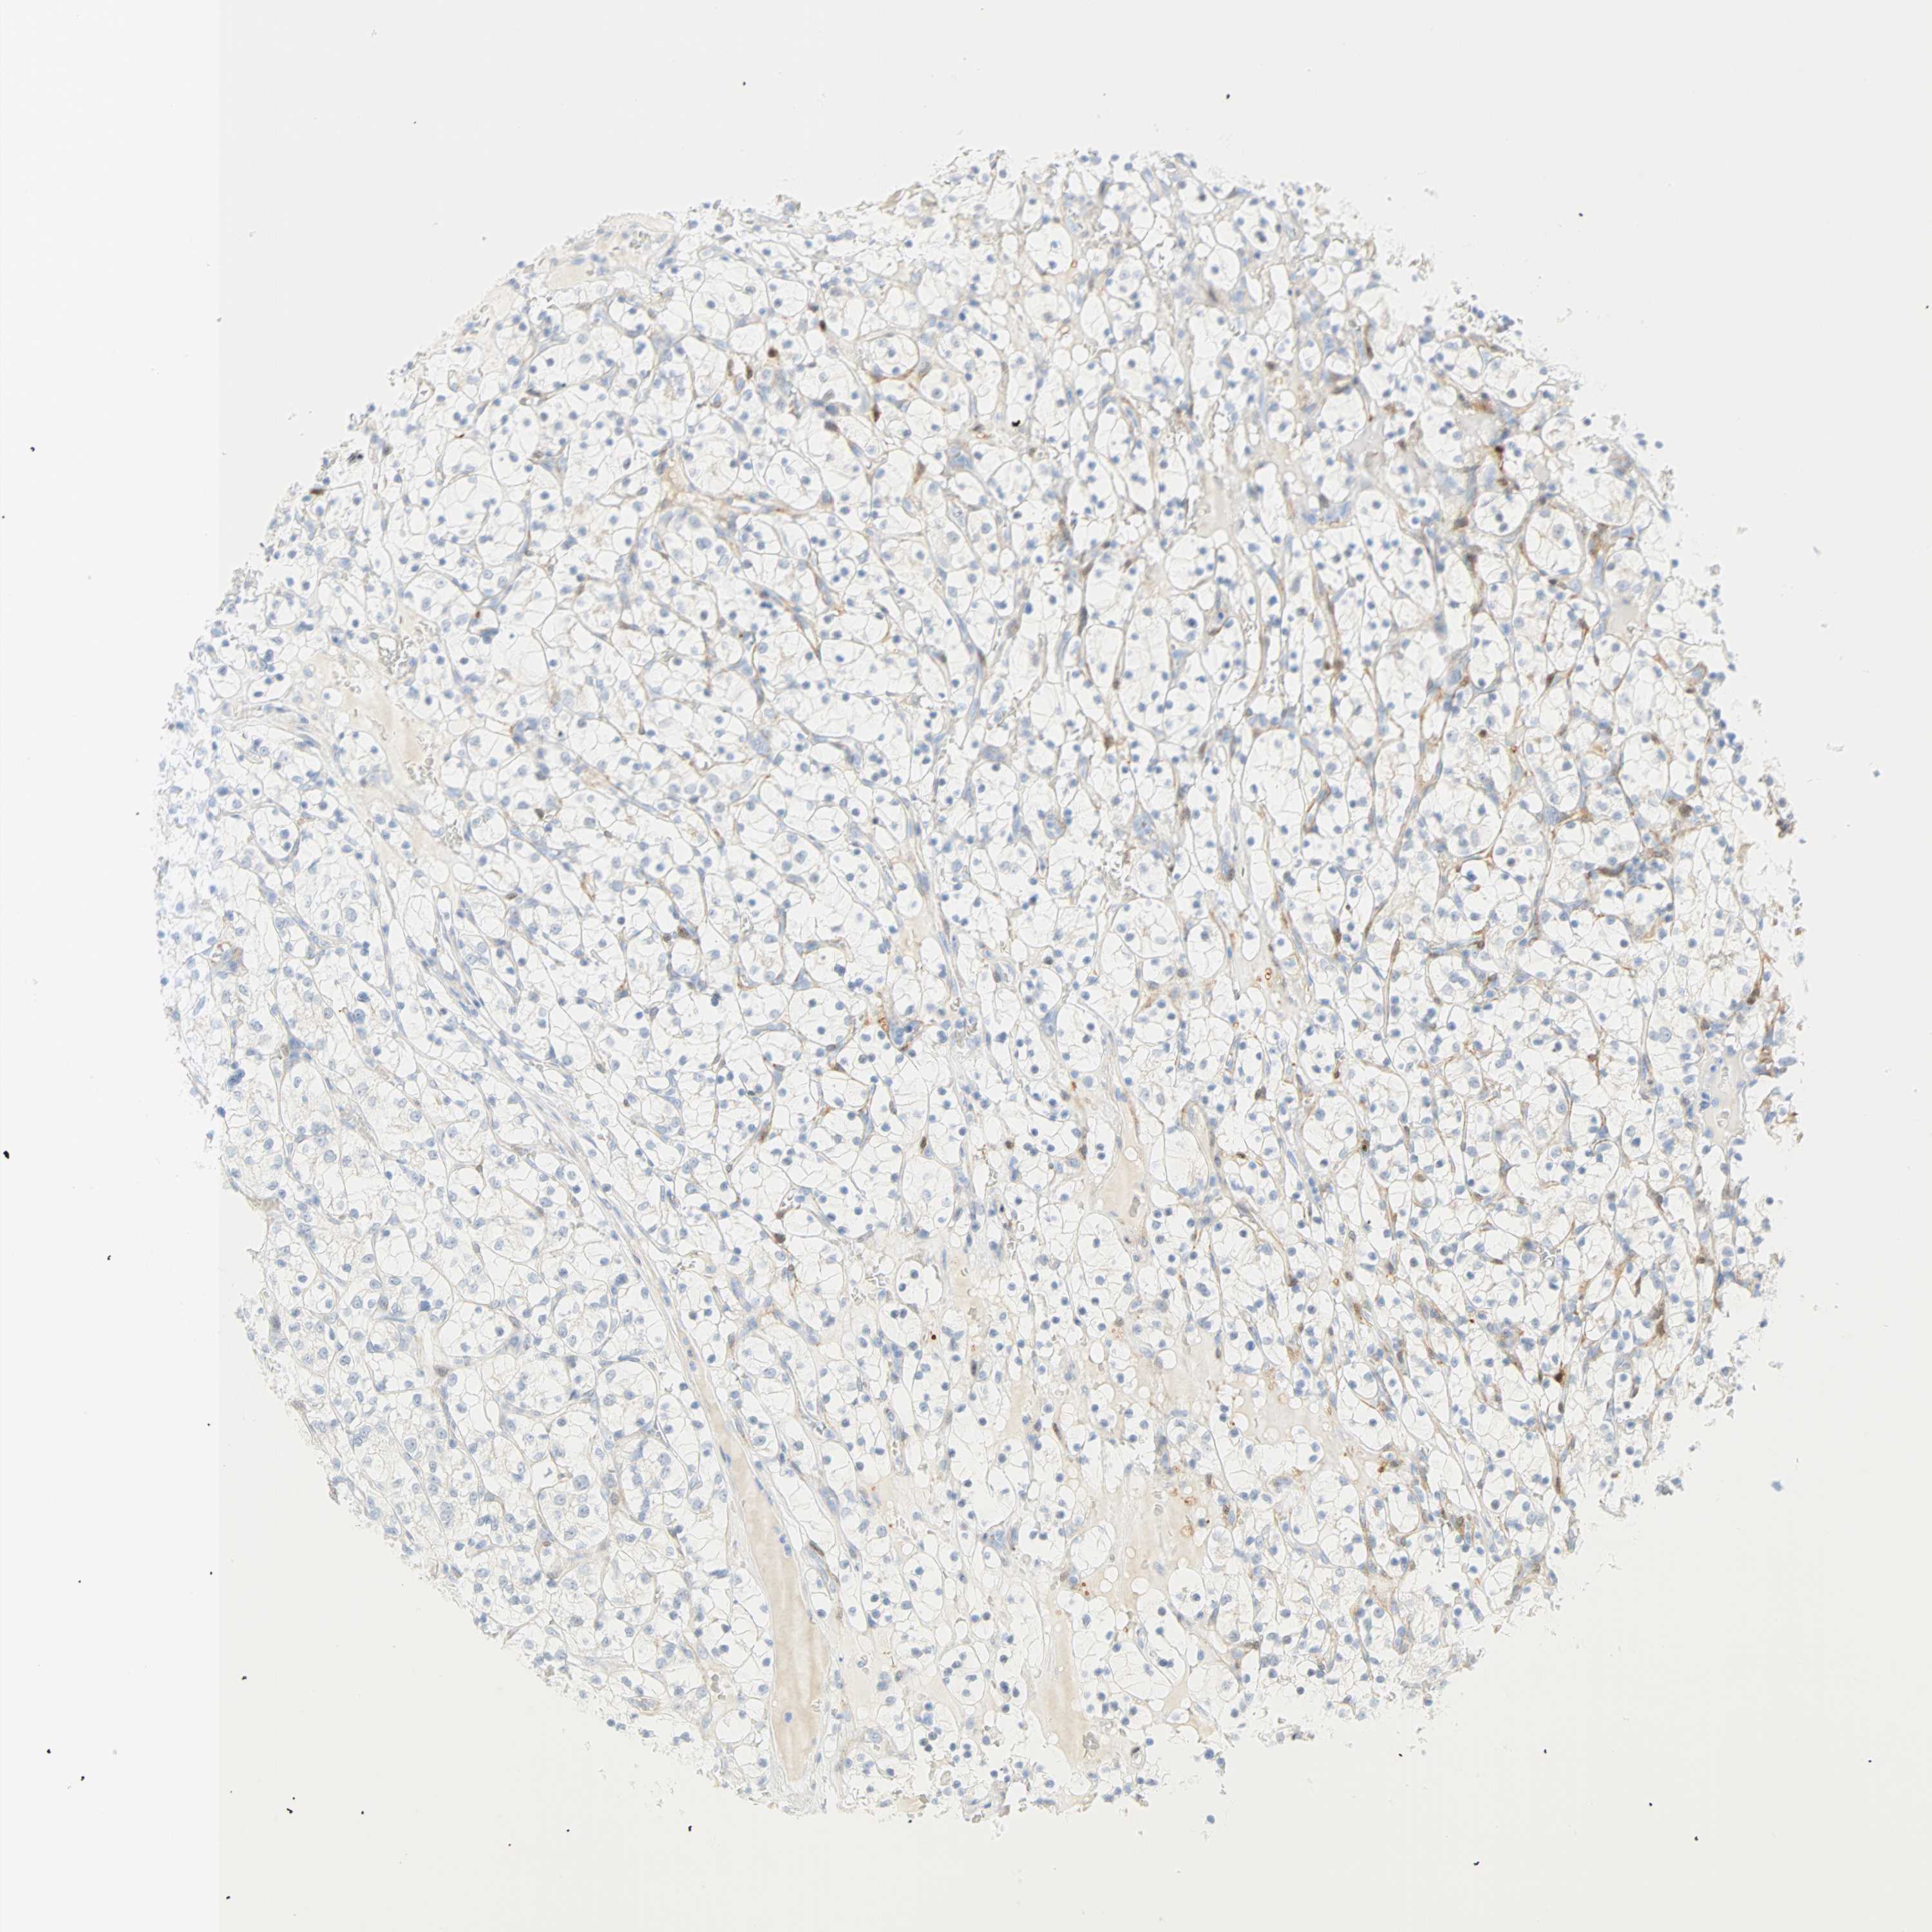

TCGA RNA samplesi

RNA-seq data is reported as average FPKM (number Fragments Per Kilobase of exon per Million reads), generated by the The Cancer Genome Atlas (TCGA) .

Normal distribution across the dataset is visualized with box plots, shown as median and 25th and 75th percentiles. Points are displayed as outliers if they are above or below 1.5 times the interquartile range. FPKM values of the individual samples are presented next to the box plot.

Average pTPM 26.3

Number of samples 521